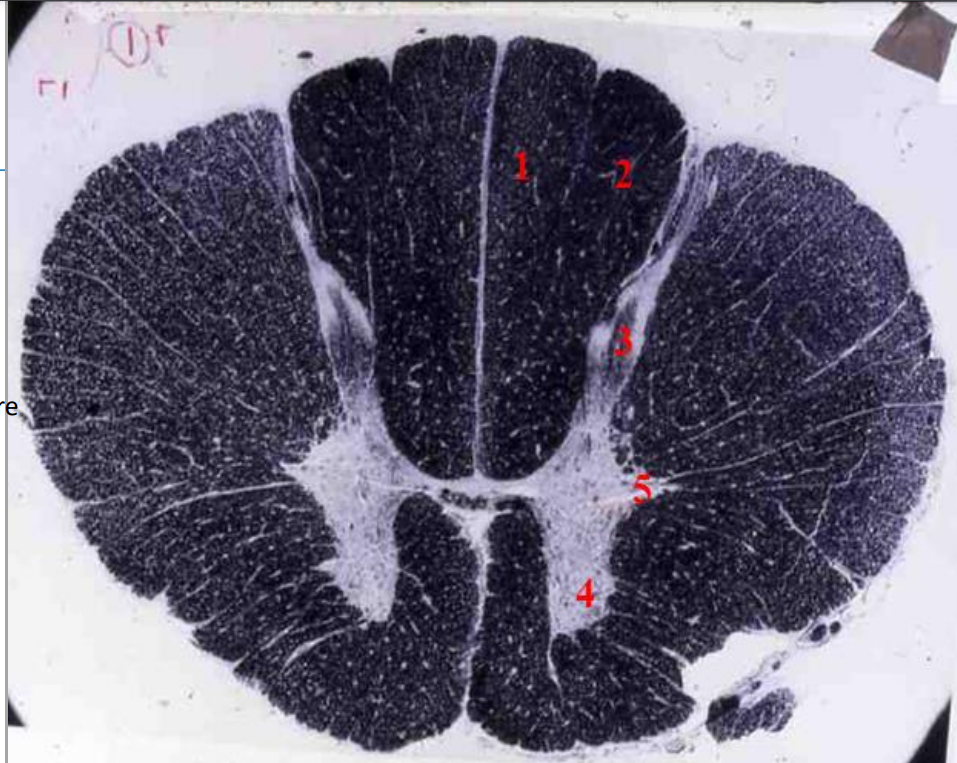

5

Q

identify weigert

A

thoracic cord

- Fibre tracts are larger

- Grey matter is scanty as no limb plexuses

How well did you know this?

1

Not at all

2